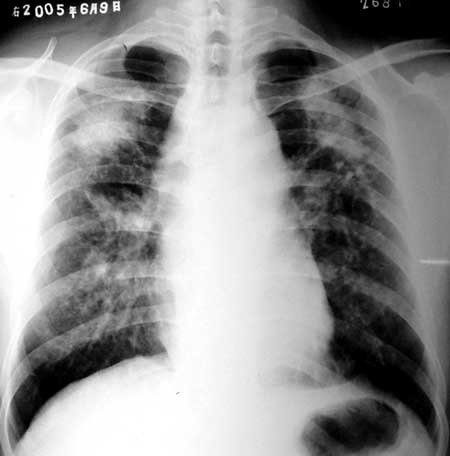

患者,男,46岁,咳嗽10多天。其他病史不详,请大家讨论!

患者,男,46岁,咳嗽10多天。其他病史不详.双上肺见较对称的长片团影,右侧较左侧大。另外双肺似可见小点结增密影显示,可见气肿征,心影示相对狭小。考虑尘肺[警惕伴发肺结核可能或炎症]

两上肺对称性块状密度较高影,呈八字形分布;两中下肺可见网结状密度增高影,两肺门影增大。两肺底部及肺尖透亮度增高。

影像学改变符合尘肺改变,请补充职业史。

两肺上叶病灶对称性分布,可见粟粒状、团片状及条索状影。

从影像上看象一个尘肺。

鉴别诊断,结核。

[emb20]大家都正确!!!患者是打隧道工,已确诊“矽肺”6年。再次[emb20]

两肺弥漫性细粟粒状及条索状影,在两上肺融合成团(矽肺结节以两上肺分布多见)。符合矽肺的影像学表现。合并结核不能除外。请结合有无职业病病史。